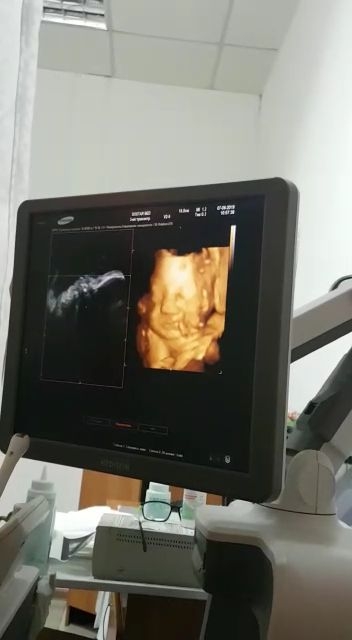

Моя малышка ❤❤❤😊😊😊

07.06.2019